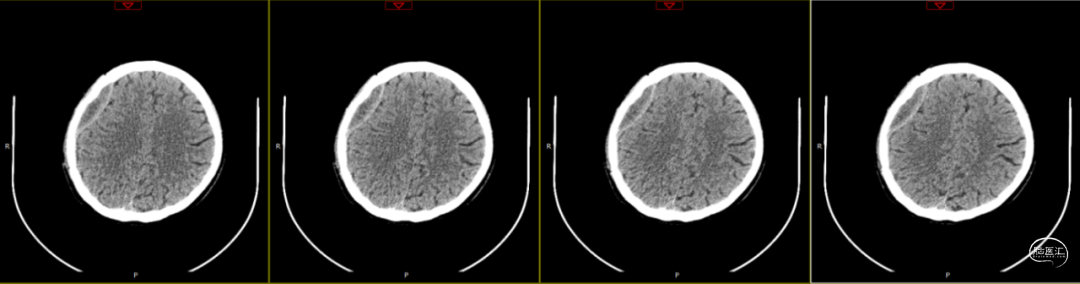

因患者局部头皮逐渐膨隆,且头皮疼痛,于术后89天再次入院。体查可触及头皮下异常物质存在,考虑头皮下积脓并硬膜外脓肿可能,患者无发热,血常规、C反应蛋白、降钙素原等感染指标均为在正常范围。

第1次术后88天,即第2次入院前1天复查(如上图),经反复沟通病情,病人及家属仍拒绝去除骨瓣清创手术,但同意进行手术清创。术中见右侧额部皮下炎性肉芽组织增生,伴有少量分泌物流出,骨瓣下见乳白色脓性分泌物,未闻及明显异味,收集脓性液体送细菌培养、涂片检查,局部硬膜增厚,较多炎性增生组织于局部硬脑膜黏连紧密,缓慢刮除局部异常增生组织后,低功率双极电凝行硬脑膜止血,骨瓣可见右侧额部外板局部被侵蚀,清理表面异物后,使用双氧水浸泡冲洗,并浸入碘伏液中消毒;彻底清除硬膜外、骨缘及右侧额部皮下增生异常组织,额顶部愈合不良刀口予以局部清创,反复使用双氧水及稀释后碘伏溶液冲洗创面,更换钛板及钛钉,还纳骨瓣并固定,皮下留置负压引流管1根,缝合逐层。术后使用万古霉素静脉抗炎治疗,留取术中脓性分泌物进行细菌培养及涂片检查(培养及检验均呈阴性)。

第2次术后第1天复查颅脑CT资料(第1次术后92天)(如上图)。